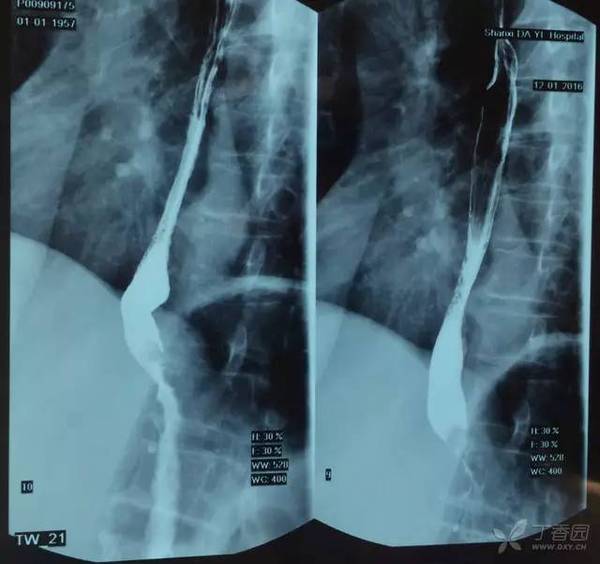

图 4 胃镜

胃镜结果示:距门齿 38-40 cm 食管下段至贲门口病变,食管下段贲门癌,病理结果示:腺癌,累及食管下段,HER-2(3+)。